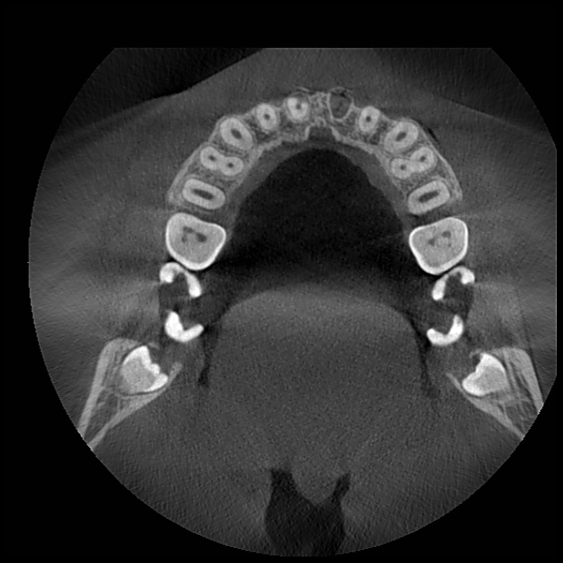

Компьютерная томография зуба позволяет получить всесторонний снимок для сбора полных данных о его состоянии. 3Д снимок челюсти позволяет оценить состояние еще не прорезавшихся зубов, корневых каналов, внутренних повреждений. Его используют при терапевтическом, ортодонтическом, ортопедическом, хирургическом лечении и в детской стоматологии.

3Д рентген зуба гораздо лучше обычного снимка. Каждый зубной ряд имеет массу анатомических особенностей, которые необходимо учитывать при лечении. Их нельзя увидеть невооруженным взглядом и даже на рентген они попадают не полностью, но КТ высветляет все подробности.

В отличие от рентгена, где изображение получается плоским, 3Д-модель врач может повернуть под любым углом, чтобы увидеть все детали. А главное, здесь отсутствуют искажения и помехи, которые могут повлиять на результат лечения.